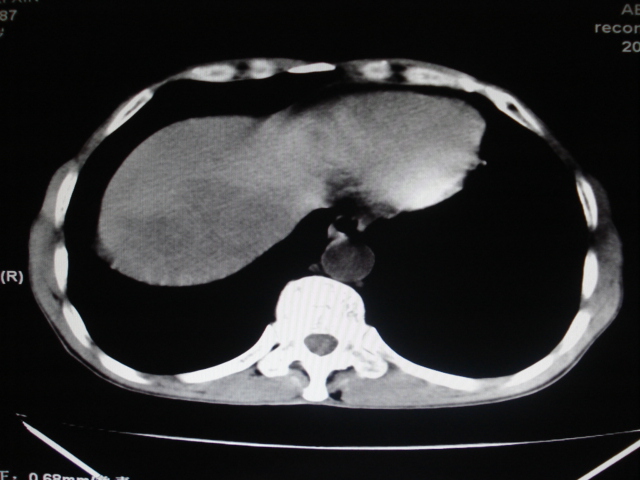

标题: CT24041:肝脏占位,请会诊!

男性,62岁。肝右叶占位,平扫及增强如下,延迟期为15分钟扫描。